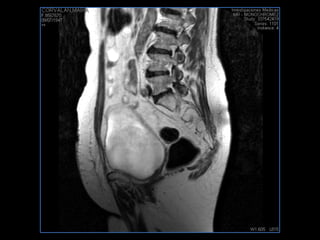

PROTOCOLO abdomen COR T2, AXIAL supresion grasa AX T1 +SAG T2  CON   GADOLINIO :  COR T1+AX T1(DIN) SAT: NO  FASE: RL THK: 6MM  COIL:  GAP: (FACTOR 1.4) 2MM FOV: 40 CM NEX:2 SINCRONIZACION RESPIRATORIA EN 3 O 4 CICLOS ALE

PROTOCOLO pelvis SAG T2, Y FAT SAT (FINOS) AXIAL T1  AX FAT SAT CON   GADOLINIO :  AX T1 Y COR T1 SAT: NO  FASE: RL THK: 3MM  COIL:  GAP: (FACTOR 1.4) 1MM FOV: 40 CM NEX:2 SINCRONIZACION RESPIRATORIA EN 3 O 4 CICLOS ALE